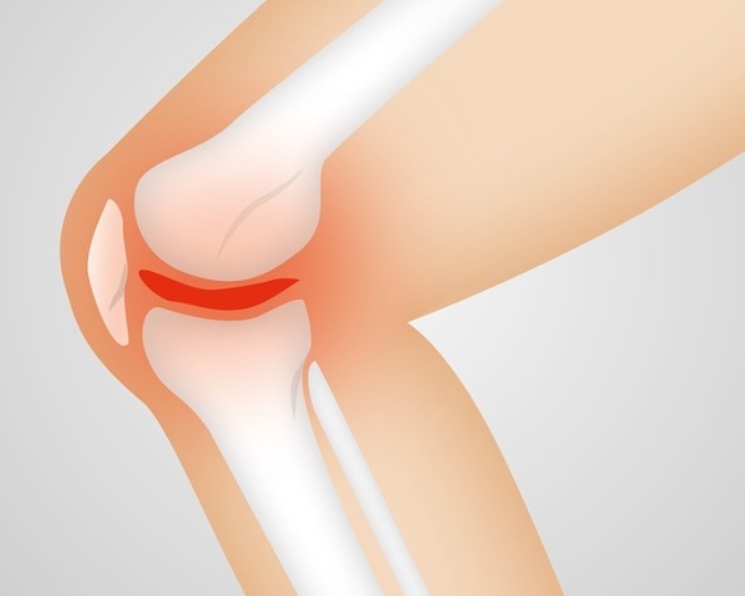

관절염은 뼈와 뼈를 연결하는 관절 부위에 염증이 생겨 통증과 부종, 움직임 제한을 일으키는 질환입니다. 관절염 초기증상 원인은 다양하지만 크게 퇴행성 관절염과 류마티스 관절염으로 구분됩니다. 퇴행성 관절염은 관절을 오래 쓰거나 체중 부담, 외상 등으로 연골이 점차 닳아 없어져 생기고, 류마티스 관절염은 면역체계 이상으로 자신의 관절을 공격해 손상시키는 질환입니다. 염증이 생기면 관절 주위의 활액막이 붓고, 연골이 손상되며, 시간이 지나면 뼈까지 변형이 올 수 있습니다. 초기에만 잡아도 진행 속도를 늦출 수 있다는 점에서 조기 진단이 필수입니다.

퇴행성 관절염 초기증상

퇴행성 관절염은 관절 연골이 점차 닳아 없어지면서 생기는 질환으로, 나이와 사용량이 주요 원인입니다. 초기에는 특정 동작 후 통증이 나타나지만 쉬면 완화됩니다. 그러나 진행되면 쉬어도 통증이 남고, 관절 모양이 변형되기 시작합니다. 관절이 뻣뻣해지고, 무릎이나 손가락을 움직일 때 마찰음이 들리기도 합니다. 조기에 근육 강화 운동과 체중 조절을 하면 진행 속도를 늦출 수 있습니다.